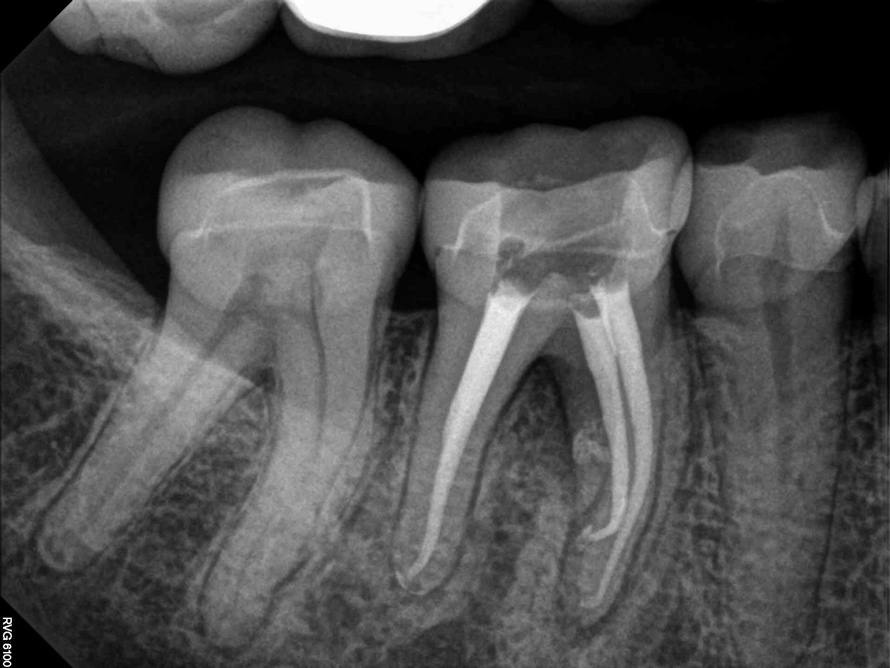

Fig 2. Tooth No. 14 was treated with silver points. In Figure 2, tooth No. 18 with mesial canals treated with Sargenti paste. The hallmark radiographic appearance of this technique is the light radiopacity within the canal system, as in Figure 3.

Figure 2

No obturation material nor method for placement available today is truly ideal. Though the dental manufacturing industry periodically introduces new materials with promise, many have been abandoned given major deficiencies in their efficacy or safety.  For example, silver points were once well accepted as root filling materials, but were abandoned decades ago due to moisture-related corrosion creating leakage and staining.4 Additionally, silver points proved especially difficult to remove during orthograde retreatment procedures due to the corrosion (Figure 2). Other historic techniques, like the now infamous paraformaldehyde-based Sargenti Method, proved dangerous due to toxicity to the adjacent periapical and surrounding tissues5 (Figure 3). More recently, the technique of complete bioceramic cement obturation has been developed. Though useful with open apices for apexification or in repairing other root deficiencies such as strip perforations, its inability to be removed readily from the root canal system means it should be reserved for those cases lacking suitable alternatives.6